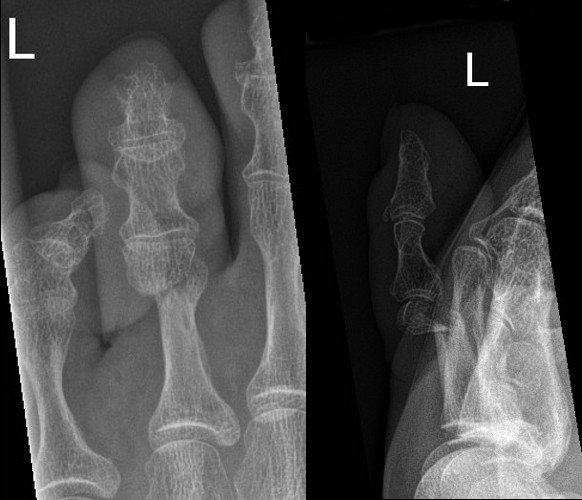

Angulated Salter-Harris II fracture of 5th proximal phalanx

Dorsally displaced transverse fracture of neck of 3rd proximal phalanx

- Consider reduction if significantly angulated.

- Buddy strap and Darco walking shoe or sturdy shoes with no specific follow up.